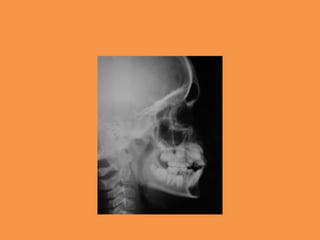

Fig.1a-b Intra-oral photographs

Fig.2 Panoramic radiograph showing

impacted maxillary central

incisor and mesiodens in region of 21